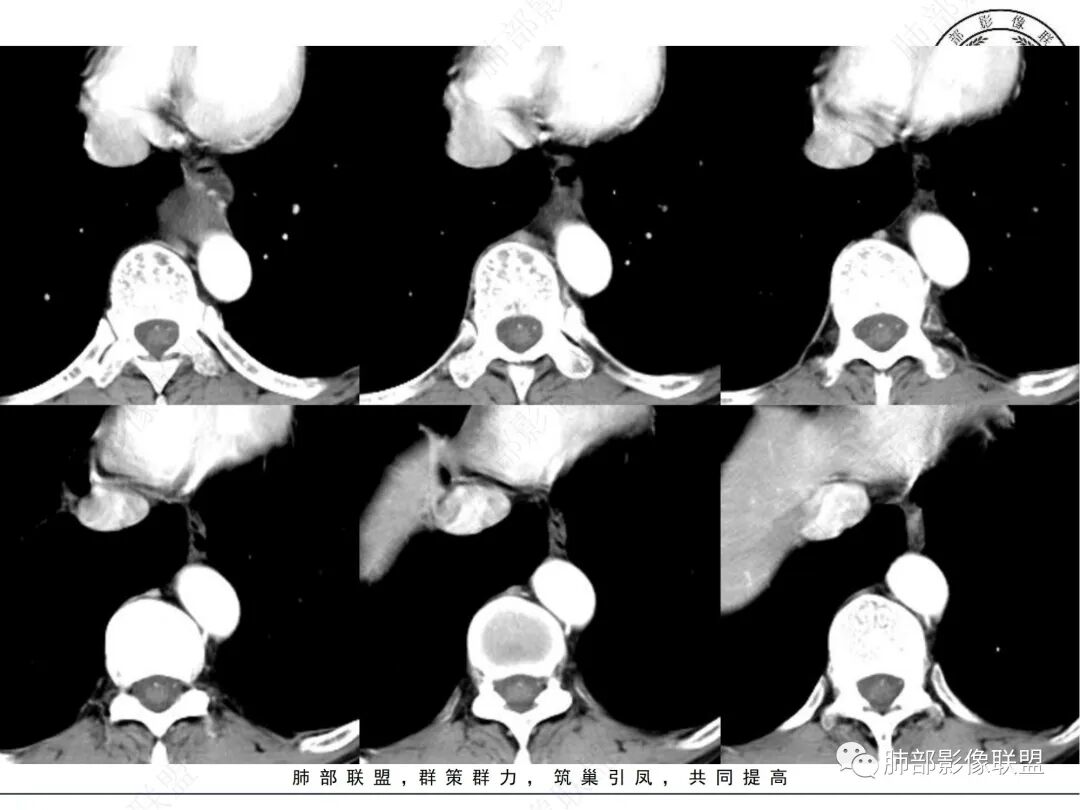

临床:中老年男性,体检发现后纵隔占位,

影像表现:后纵隔类圆形软组织肿块,增强扫描不均匀强化,内部可见囊变区及实性区,实性区明显延迟强化,边界清晰,邻近左心房及食管受压改变,

定位定性:后纵隔良性肿瘤,

诊断:神经源性肿瘤,神经鞘瘤

1. 中老年男性,偶然发现后纵隔占位(没有吞咽梗阻等消化道症状)。实验室检查无特殊。

2. 后纵隔类圆形囊实性占位,整体圆张力大,边界光整,增强后不均匀强化(似乎形成AB区?),轻度强化囊性区明显强化实性区,病灶边缘有明显强化血管影,与食道前壁界限不清,且食道明显受压,主动脉血管受压有脂肪间隙。考虑神经源性肿瘤,神经鞘瘤的可能。